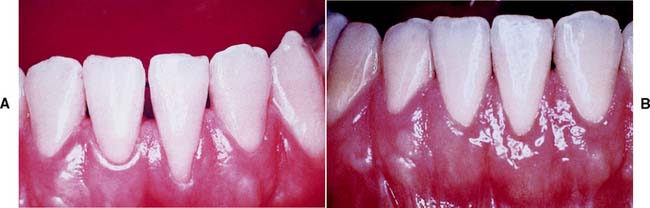

The width of the band of attached keratinized gingiva may be increased by surgical grafting as part of mouth preparation before restorative treatment. Although the amount of gingiva necessary for long-term periodontal health is open to debate and definite conclusions are difficult to draw, comprehensive evaluation of the amount of attached keratinized tissue is always advised.32,33 It is recommended34,35 that a tooth to be treated with a restoration extending into the gingival sulcus have approximately 5 mm of keratinized gingiva, at least 3 mm of which is attached gingiva. Where less keratinized gingiva is present, or in areas of localized gingival recession, a grafting or other gingival augmentation procedure should be considered.

A free (detached) autogenous gingival graft (Fig. 6-13) is used to increase the width of attached gingiva in areas where it is deemed inadequate. The donor site most commonly used is the hard palate, although any area of keratinized tissues, such as an edentulous ridge or the retromolar pad, may be suitable.

Fig. 6-13 Free autogenous gingival graft. A, Planned abutment tooth lacking adequate keratinized gingiva. B, The recipient site is prepared. C, The graft is sutured to place. Some apical adjustment is needed around the premolar before application of the surgical dressing. D, The healed graft. (Compare the width of attached keratinized gingiva here with that in part A.) The defective restoration can be treated at this stage.